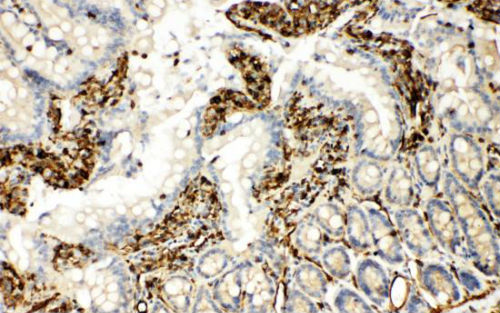

作者首先发现这样一个现象:患有脓毒症(一种系统性炎症)的患者外周血细胞中MST4的表达量要明显低于健康人群,其IL-6的表达量与MST4的表达量具有高度的反向相关性。之后,作者通过体外LPS刺激不同类型的小鼠原代巨噬细胞以及体内刺激小鼠并检测不同组织器官中的MST-4的表达量。结果显示:在接受刺激之后,MST4会有一个快速的上升。